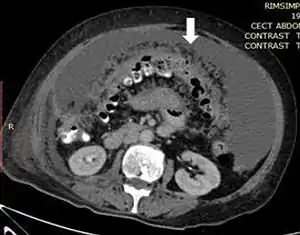

| Axial abdominal computed tomography featuring omental caking due to peritoneal carcinomatosis | |

Due to the variety of symptoms experienced by patients with omental caking,[5] omental cakes are most frequently discovered on abdominal computed tomography (CT) or ultrasound. Plain film radiography (X-ray) is not a suggested modality for investigating the spread of cancerous cells in the abdomen due to the poor spatial resolution amongst soft-tissue densities. Contrast resolution obtained through CT allows radiologists to investigate omental caking for morphology, intraperitoneal fluid, and regional lymphadenopathy assists in proper diagnosis so clinicians, surgeons, and oncologists can plan the appropriate course of treatment.[8]